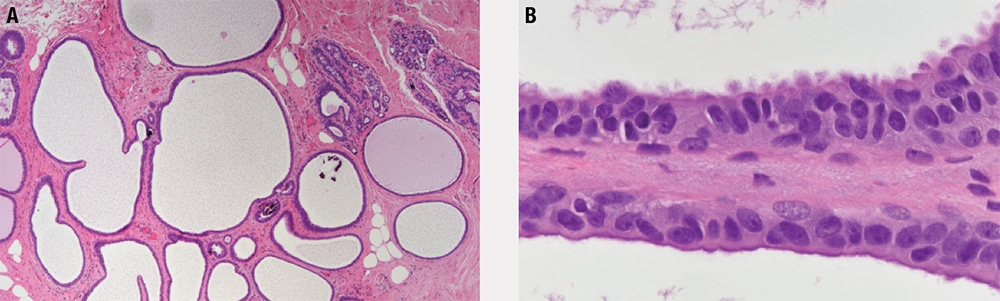

- There are expanded terminal duct-lobular units in a pattern similar to blunt duct adenosis/columnar cell alteration; however, the luminal spaces tend to be more rigid and round.

- As in blunt duct adenosis/columnar cell alteration, the cells may be columnar or cuboidal, and apical cytoplasmic snouts and luminal calcifications are often present.

- The luminal cells (Figure 5-8) are monomorphic, contain small nucleoli, and have nuclei that are enlarged, rounded, and without polarity; these are the main features that distinguish FEA from blunt duct adenosis/columnar cell alteration, and these are the features that it has in common with ADH/DCIS.

- The epithelial proliferation is flat (it may be pseudostratified but is not stratified), with no architectural complexity or bridging, in contrast to ADH/DCIS.